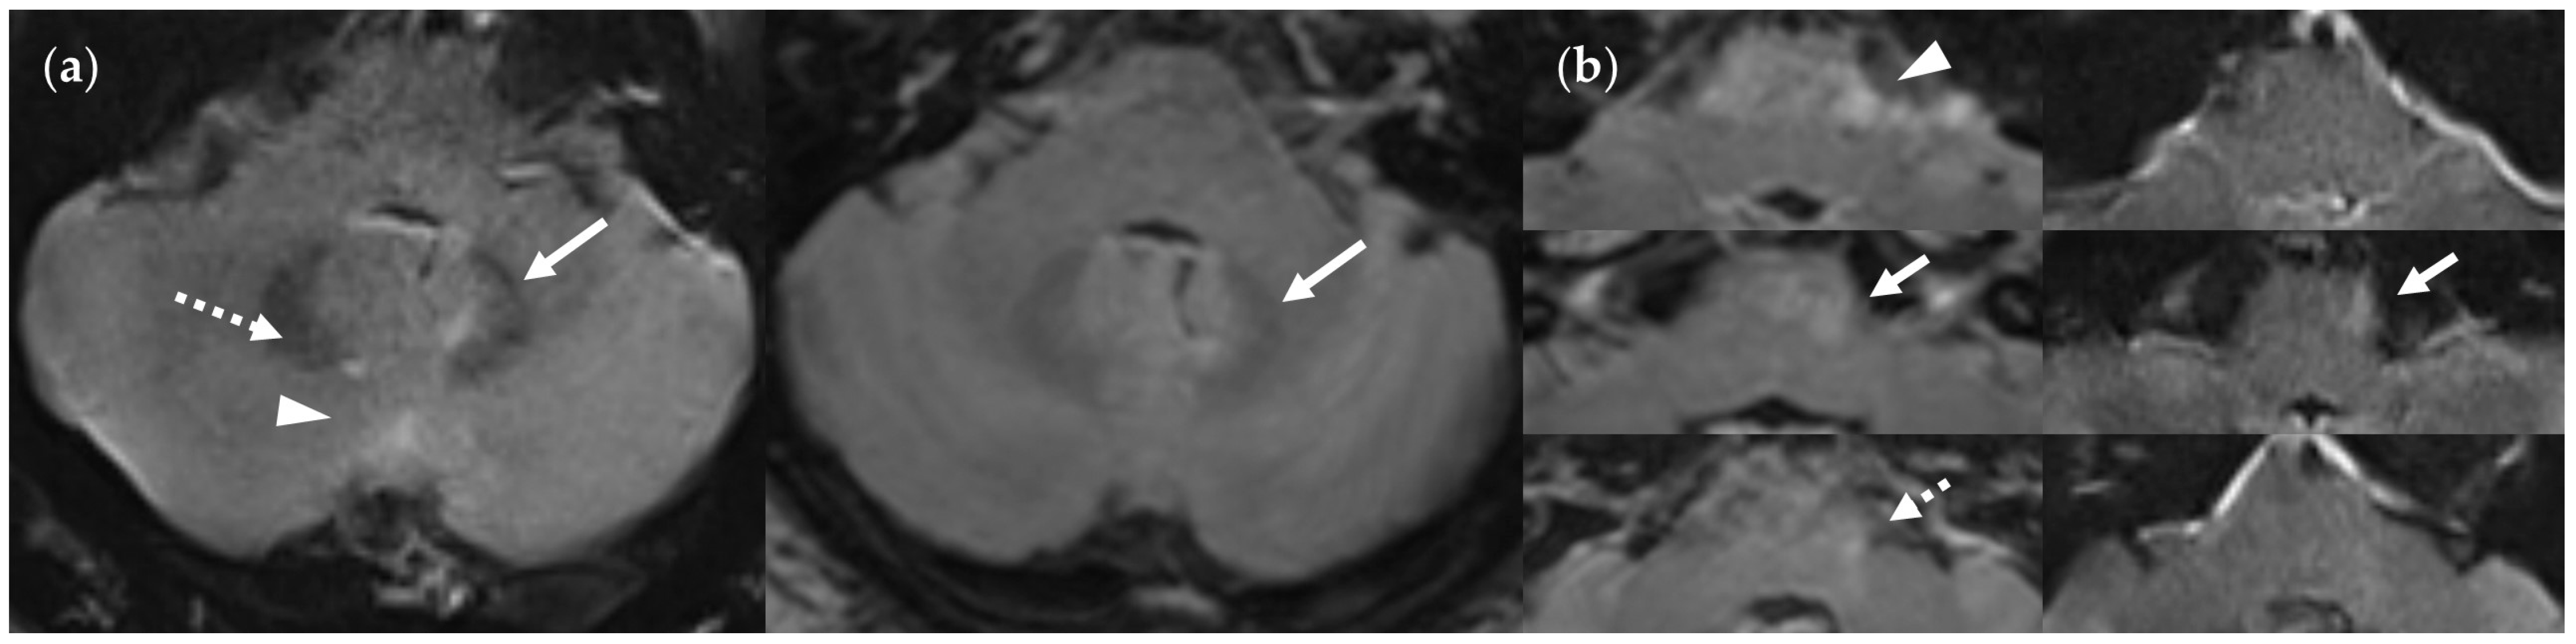

4.3. Limitations of the FLAIRUF Images

4.4. Considerations on Ratings for Lesion Conspicuity in FLAIRUF

4.5. Outcomes Correlated with Technical Features